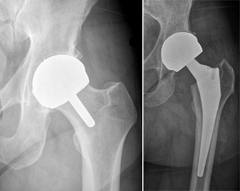

The company ORTHOPEDIC NIKIFOROV was founded in 1998 by the candidate of medical sciences. doctor of orthopedic-traumatologist of the highest category Nikiforov IA Owing to high professionalism and results of work, ORTONIC has gained well-deserved reputation and reputation among colleagues and population of Dnepropetrovsk region and CIS countries (Russia, Moldova, Armenia, etc.). The principle of the enterprise is NO IMPOSSIBLE, it is based on knowledge, experience and active implementation of modern technologies in orthopedics and traumatology. Conservative methods of treatment include individual selection of medicines, therapeutic blockades, manual therapy, massage, physiotherapy (vibration table, magnetotherapy, bioptron, electromyostimulation, etc.), rehabilitation with the suggestion of the necessary concomitant devices and means for the fastest recovery (corsets, bandages, various joint fixators, crutches, walking sticks, etc.). Various minor invasive interventions (chymonucleolysis, vertebroplasty, kyphoplasty, percutaneous nucleoplasty using cold plasma) that are performed on an outpatient basis are successfully used to treat problems associated with spine pathology. The latest modern treatment methods introduced in our company are endoscopic operations using the TYSSES technique of Joimax (Germany) with intervertebral hernias, stenosis and other pathologies of the spine, which allow to avoid complications occurring during open operations and the accompanying general anesthesia. We have many years of successful experience in traditional and modern minimally invasive endoprosthetics of large and small joints, which remains the main direction of our activity. Our company is the exclusive representative of the German company IO International Orthopaedics Holding GmbH, which based on the already known prostheses, its ideas and technological capabilities, has developed and implemented a new concept in hip replacement - an artificial joint prosthesis (ICON). We assist interested colleagues in training the operative technique for installing an artificial joint prosthesis - ICON, both in the workplace and in Germany. For 20 years we have been successfully cooperating with Sanitatshaus Gerd Klinz ortho team, an enterprise that for 20 years has been one of the leading places in Germany for the production of functional prostheses of the upper and lower limbs, as well as cosmetic prostheses of limbs and other body parts (nose, ears, eyeballs, fingers). We have an atmosphere of friendliness and human participation. Politeness, benevolence, the desire to understand and help is the basis of our attitude towards patients. We are always glad to see you and will do our best to make you feel great! We are waiting for you at: Ukraine, Dnepr, Gagarin Ave., 13 (under reconstruction) on all questions to address: tel .: +38 (050) 488-88-92 E-mail: orthonik.ukr@gmail.com Germany, Spine Nano Klinik, Zeppelinstr. 21, Potsdam Tel. +4901801121919 E-mail: kmw.nikiforov@hotmail.de